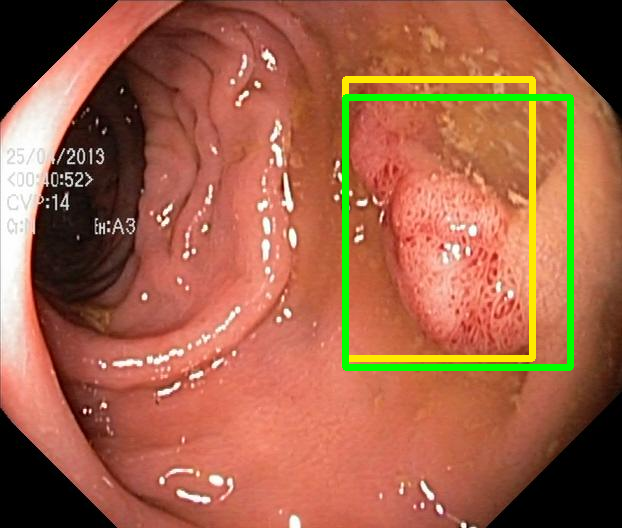

We evaluate the resulting object detection models using the test data, which is pre-processed in the same manner as the validation data, with AP@[.5:.95] (AP for conciseness), AP@.5 (AP50), and AP@.75 (AP75) computed for predicted bounded boxes with a confidence score \geq0.05. For all metrics, a higher value indicates better performance. The results are presented in Table VI, and some examples for predicted bounding boxes with a confidence score \geq0.5 are shown in Fig. 1.

Figure 1: Targets (yellow bounding boxes) and predictions (green bounding boxes) for two randomly selected instances of the Kvasir-SEG test set. For conciseness, we denote ResNet50s with RN, ViT-Bs with VT, Hyperkvasir-unlabelled with HK, ImageNet-1k with IN, MoCo v3 with MC, Barlow Twins with BT, MAE with MA, supervised pretraining with SL, and no pretraining with NA-NA.